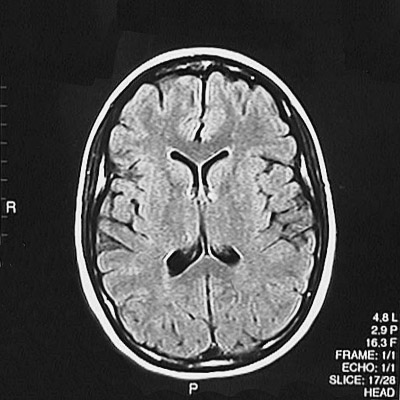

This is a normal axial FLAIR MRI scan demonstrating the frontal lobe and parietal lobe and genu of corpus callosum and splenium of corpus callosum and anterior horn of lateral ventricle and posterior horn of lateral ventricle and caudate and thalamus and putamen and internal capsule and superior sagittal sinus.